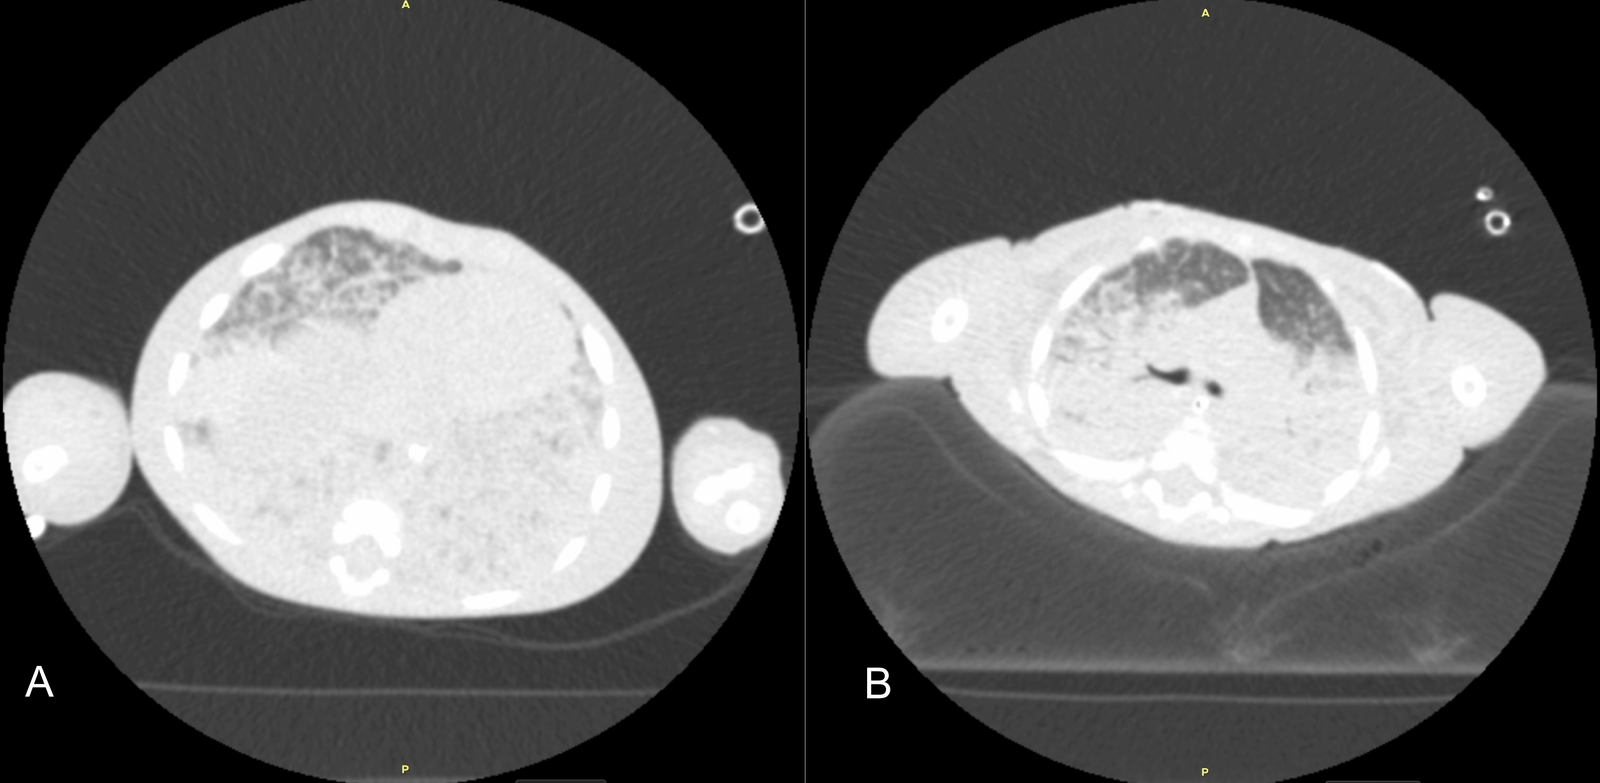

Initial diagnostic workups for immunodeficiency and metabolic diseases were normal; however, a sweat test could not be performed due to the patient's poor general condition and malnutrition. Echocardiography showed no cardiac disease, and abdominal ultrasound was normal. Due to parental consanguinity and a history of a sibling death at 9 months with similar clinical symptoms, a congenital genetic disease with associated interstitial lung disease (ILD) was primarily suspected. Consequently, clinical genetics was consulted, and Whole Exome Sequencing (WES) analysis was initiated. The severity of hypoxemia was assessed using the Oxygen Saturation Index (OSI) and the patient was diagnosed with PARDS based on acute hypoxemia, an OSI of 25, and chest X-ray findings showing new-onset bilateral diffuse alveolar infiltration and pulmonary parenchymal edema (1,2) (Figure 1). Initial axial chest computed tomography was performed at ICU admission, demonstrating diffuse bilateral ground-glass opacities and consolidations (Figure 2A, 2B). Thoracic ultrasound identified bilateral pleural effusions (7 mm on the right and 10 mm on the left). Due to elevated acute phase reactants (WBC: 57 x 109/L, CRP: 33 mg/L), antibiotic therapy was initiated with Vancomycin and Meropenem, alongside appropriate symptomatic PARDS management.

Initial axial chest computed tomography images

Figure 2. Initial axial chest computed tomography images obtained at ICU admission. A: Upper lung level demonstrating diffuse bilateral ground-glass opacities. B: Lower lung level showing extensive consolidations consistent with severe pediatric acute respiratory distress syndrome.